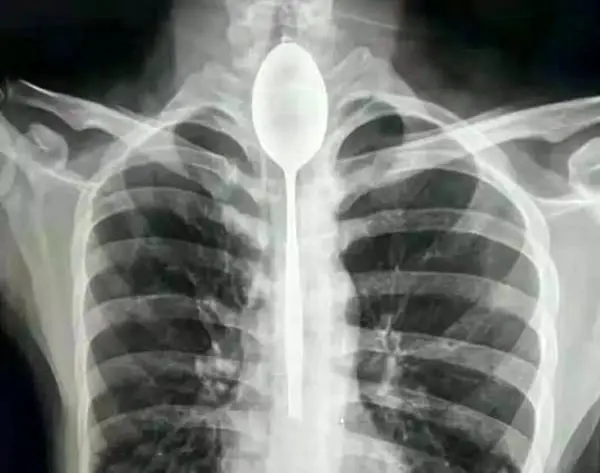

قورت دادن قاشق 20 سانتی سر شرط بندی / قاشق یکسال در گلویش بود + عکس

رکنا: مردی در یک شرط بندی احمقانه قاشق 20 سانتی را بلعید و از آنجایی که مشکلی در خوردن و آشامیدن نداشت تا یکسال این قاشق داخل گلوی وی ماند.

مرد چینی قاشق فلزی 8 اینچی را به عنوان یک شیرین کاری احمقانه در سال گذشته بلعید. قاشق در مری او گیر کرد، اما چون به راحتی می توانست بخورد و بنوشد، هرگز به دنبال کمک پزشکی برای بیرون آوردن آن نبود. او می گوید تنها چند روز پیش به علت ضربه وارد شده به قفسه سینه ، دچار درد قفسه سینه شد ؛ این جملات قسمتی از ماجرای عجیبی بود که در این بخش از سرگرمی Hobby نمناک خواهید خواند.قاشق داخل بدن مرد چینی

مردی که نامش فاش نشده است از منطقه جین جیانگ چین به پزشکان گفت :او یک قاشق فولادی ضد زنگ را در طی یک شرط درحالت مستی بلعیده . او به دوستانش گفته که می تواند قاشق را ببلعد و بعد دوباره با ریسمانی که به دسته قاشق می بندد آن را بیرون آورد . در آن زمان برای او حتما فکر خوبی به نظر می رسید، اما همه چیز طبق برنامه پیش نرفت و قاشق در گلوی او گیر کرد. به جای رفتن به بیمارستان، مرد منتظر ماند تا ببیند آیا قاشق به طور عادی از خوردن و نوشیدن جلوگیری می کند یا نه ؛ این طور نبود، پس در مری ماند تا سال گذشته.

قاشق مدت طولانی در سینه او مانده بود و براثر ضربه ای که به سینه او وارد شده بود باعث درد شدید و تنفس بدبو او شده بود . سرانجام به بیمارستان عمومی جین جیانگ رفت و به پزشکان گفت یک سال است که قاشق فلزی در مری او گیر کرده است.

دکتر یو در بیانیه ای که توسط بیمارستان منتشر شد ، نوشت:من هرگز چنین چیزی ندیده ام ؛ شوکه شده بودم.

پزشکان در بیمارستان عمومی جین جیانگ پس از بحث در مورد بهترین مسیر عمل تصمیم گرفتند که بهترین راه خارج کردن قاشق ، از طریق دهان بوده است. داروی بی هوشی به بیمار دادند و یک تیم دو ساعت تلاش کردند تا با استفاده از تجهیزات آندوسکوپی ، قاشق 8 اینچی را بیرون آوردند.